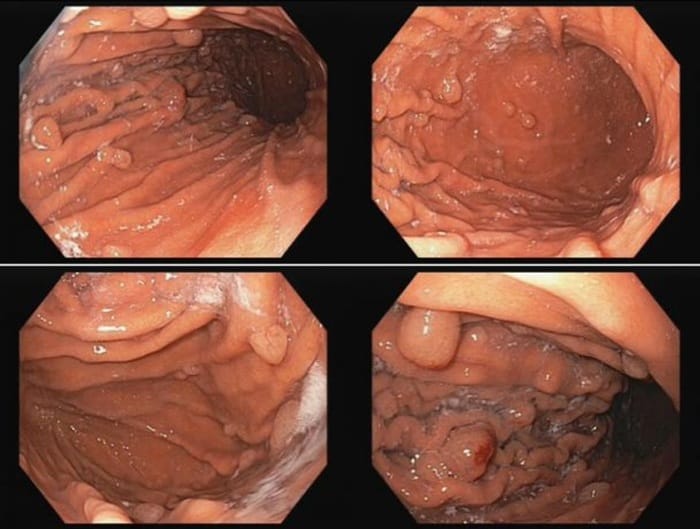

Polyp dạ dày là khối tế bào tăng sinh bất thường xuất hiện trên lớp niêm mạc bên trong dạ dày, được phát hiện qua nội soi tiêu hóa. Hầu hết polyp là lành tính, nhưng một số loại có thể tiến triển thành ung thư nếu không được theo dõi và xử lý kịp thời.

Polyp hình thành do sự tăng sinh quá mức của các tế bào niêm mạc – lớp lót bảo vệ thành dạ dày khỏi axit và enzyme tiêu hóa. Hầu hết polyp không gây triệu chứng rõ rệt, vì vậy thường được phát hiện tình cờ qua nội soi tiêu hóa, khi bác sĩ quan sát trực tiếp lớp niêm mạc, đánh giá kích thước và hình dạng polyp.

Polyp dạ dày có thể phát hiện qua nội soi tiêu hóa

Polyp dạ day có rất nhiều loại

Nội soi là phương pháp chẩn đoán polyp dạ dày chính xác và an toàn nhất